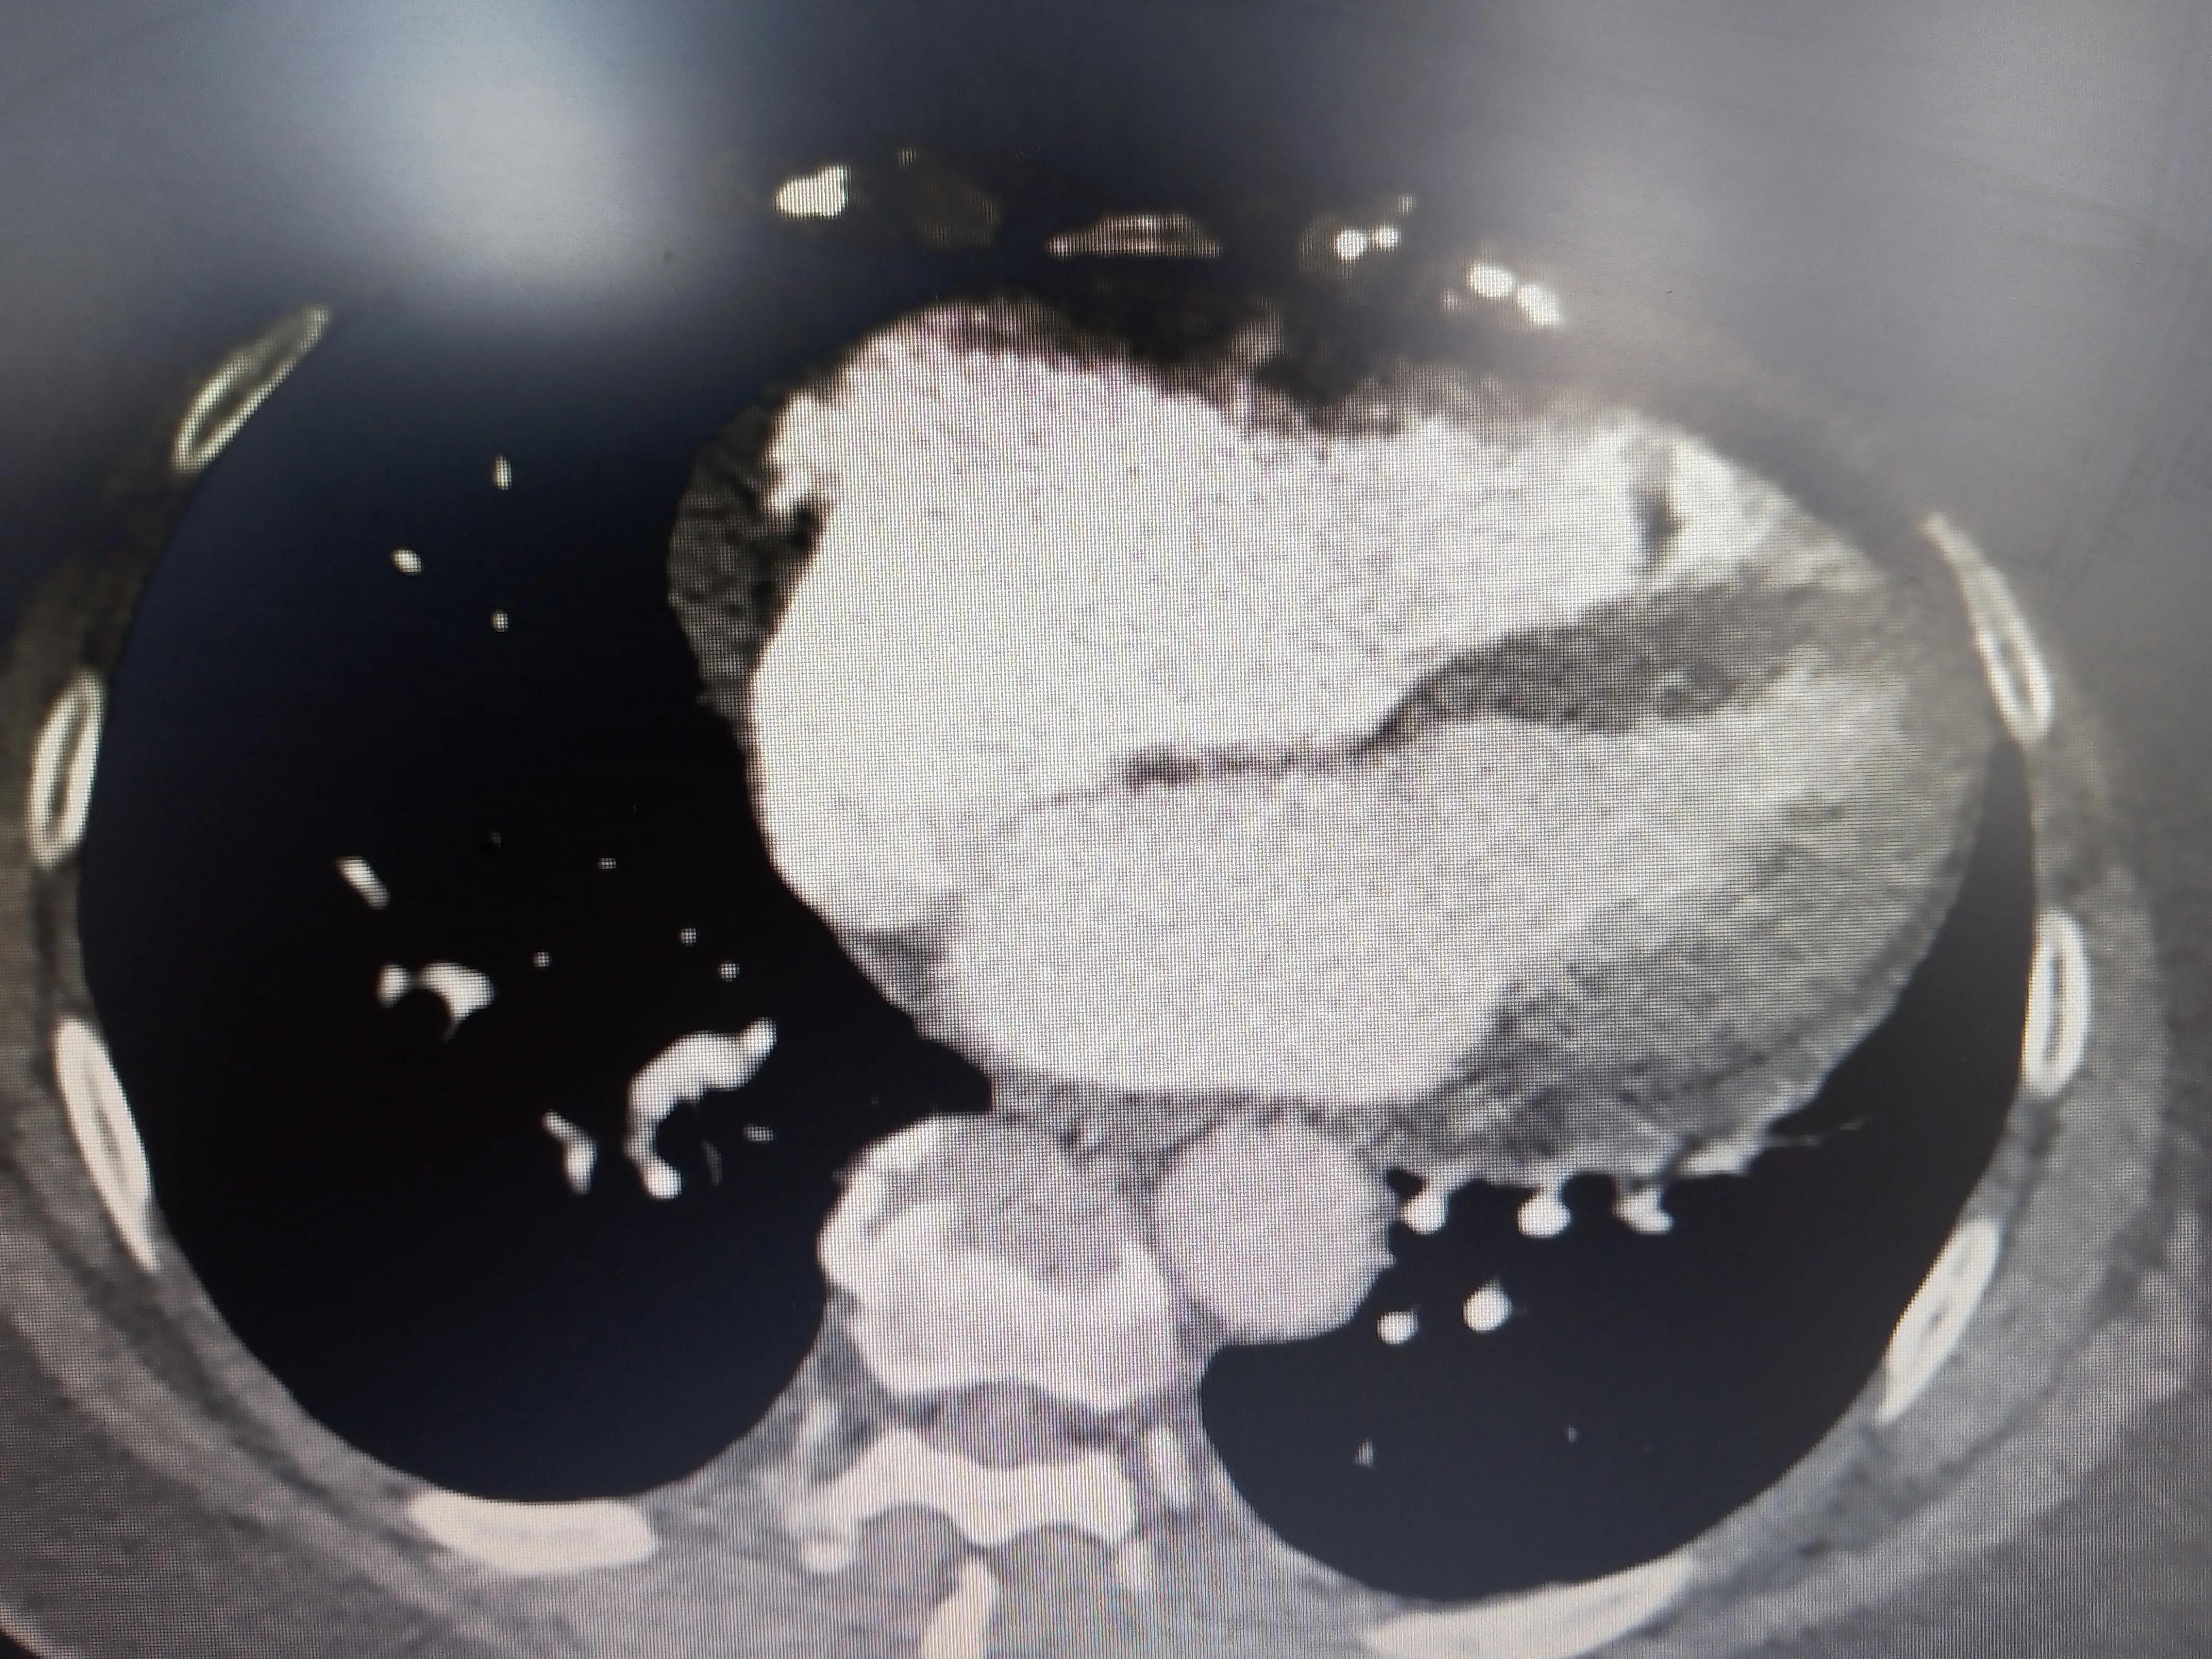

同时肺静脉CT里面发现肺里很干净,没有结节也没有明显的急性或慢性炎症;右心明显扩大导致心尖上翘。

右心明显扩大

右心明显扩大,肺挺干净的